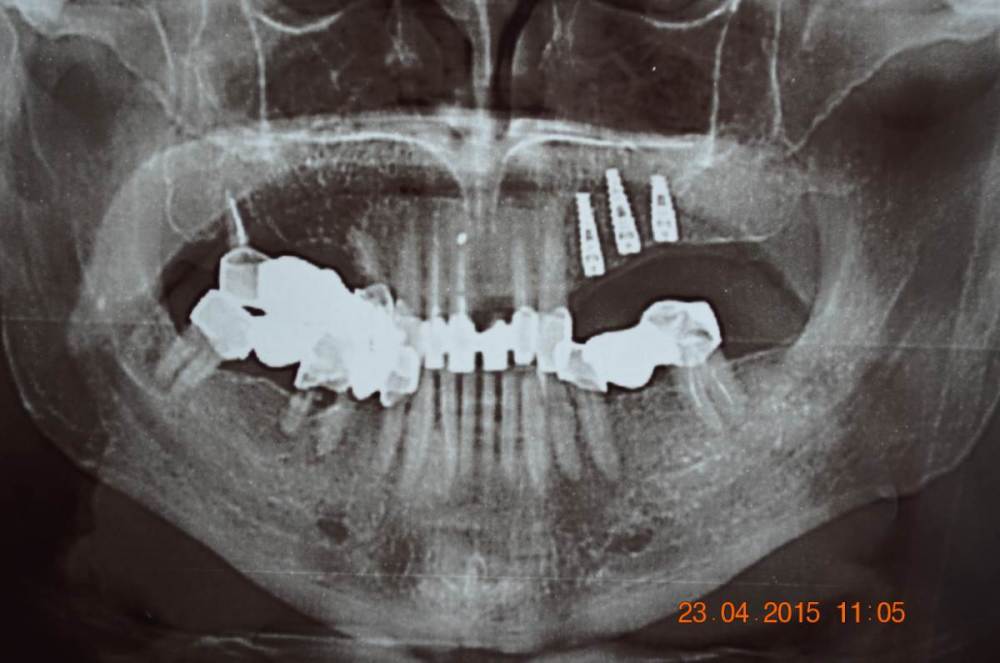

Большой Зеленый Опубликовано 7 ноября, 2022 Поделиться Опубликовано 7 ноября, 2022 Обратите внимание на даты 2 Ссылка на комментарий